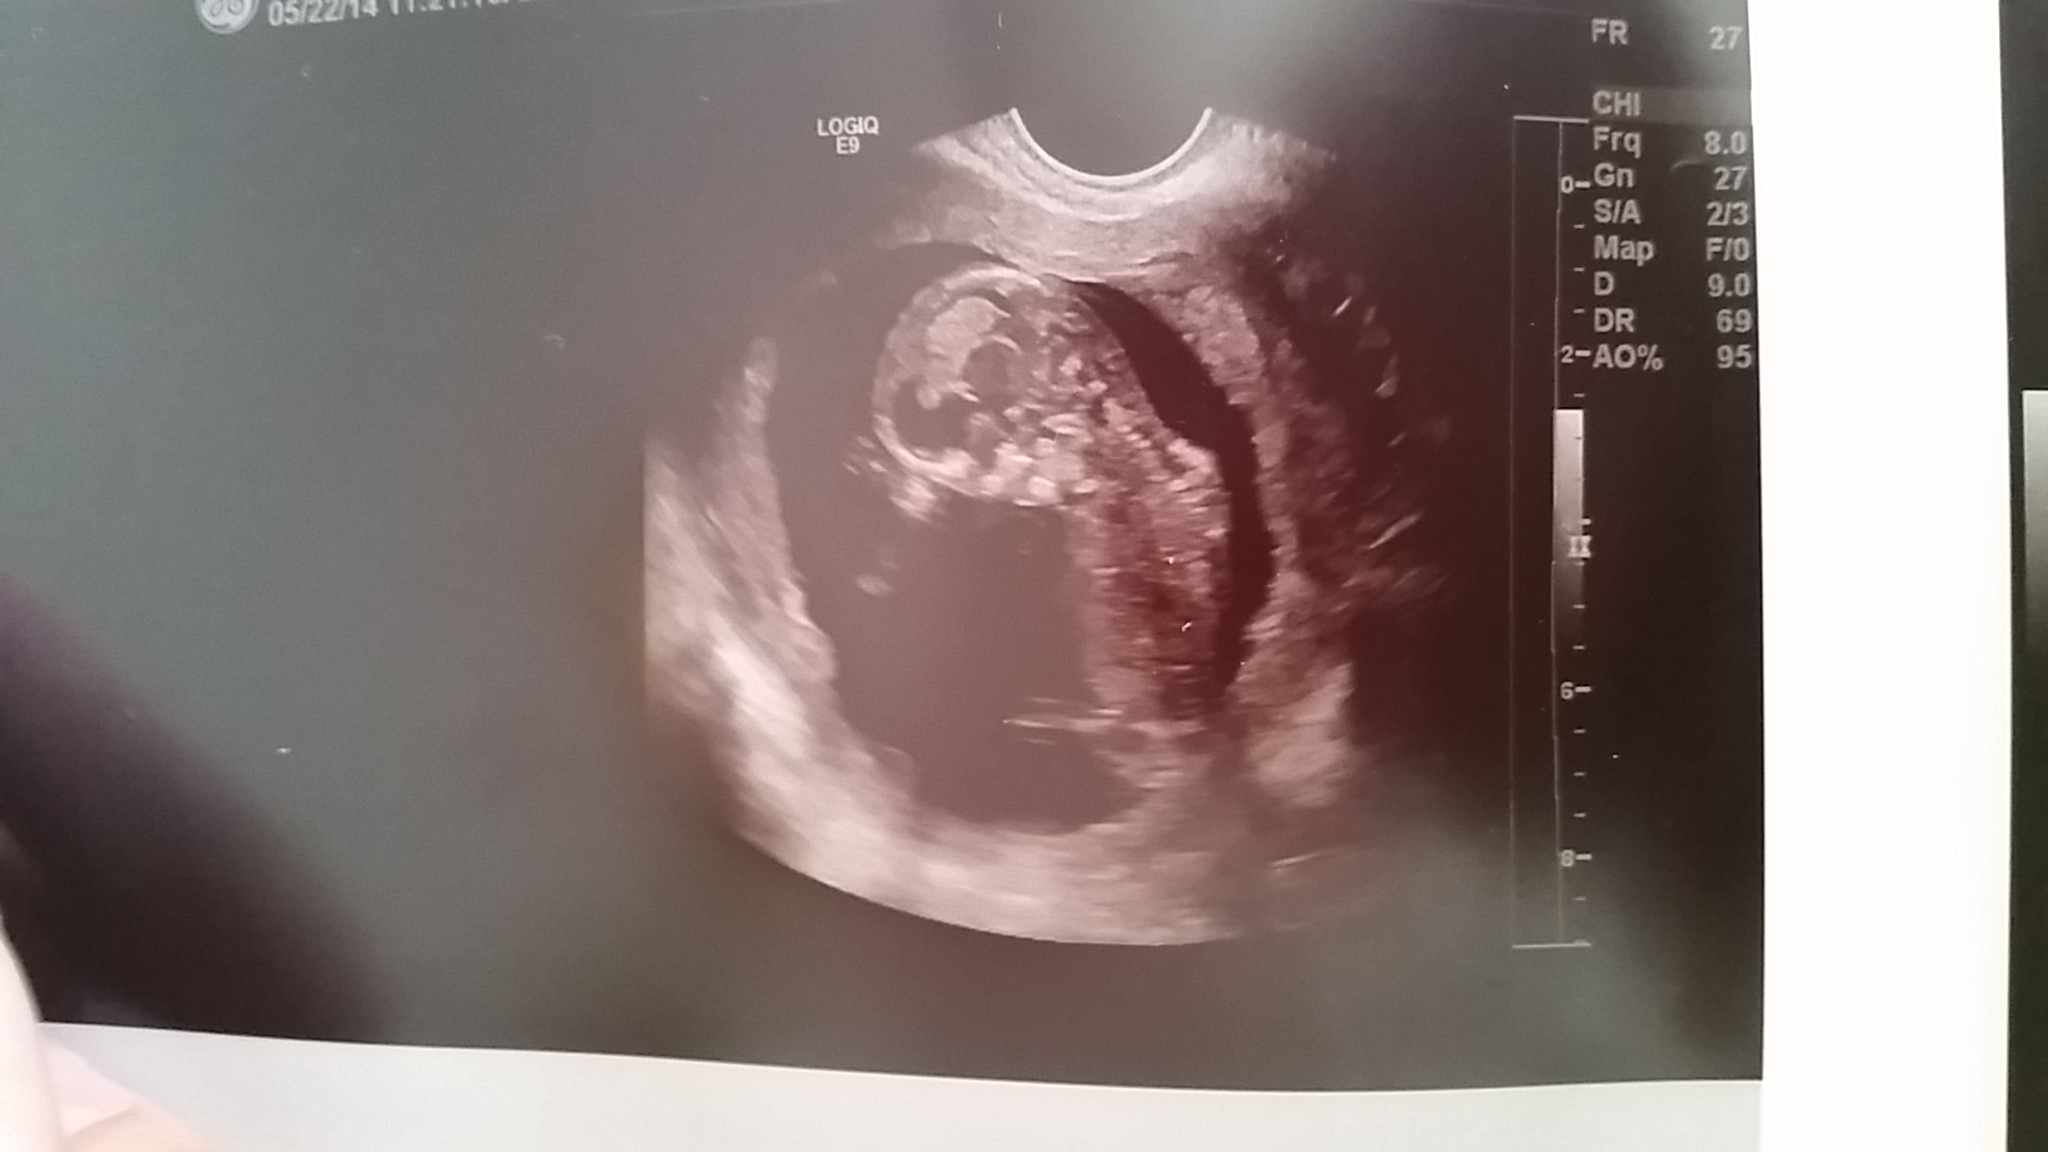

We had our early u/s and the tech is thinking it's a boy. We'd love your thoughts! (Photos are at 12 or 13 weeks- tech said I'm measuring 12 wk 3 days, but gave us a due date of Nov 25th, which to me would seem to mean we're 13 weeks...?) Thank you and cheers!